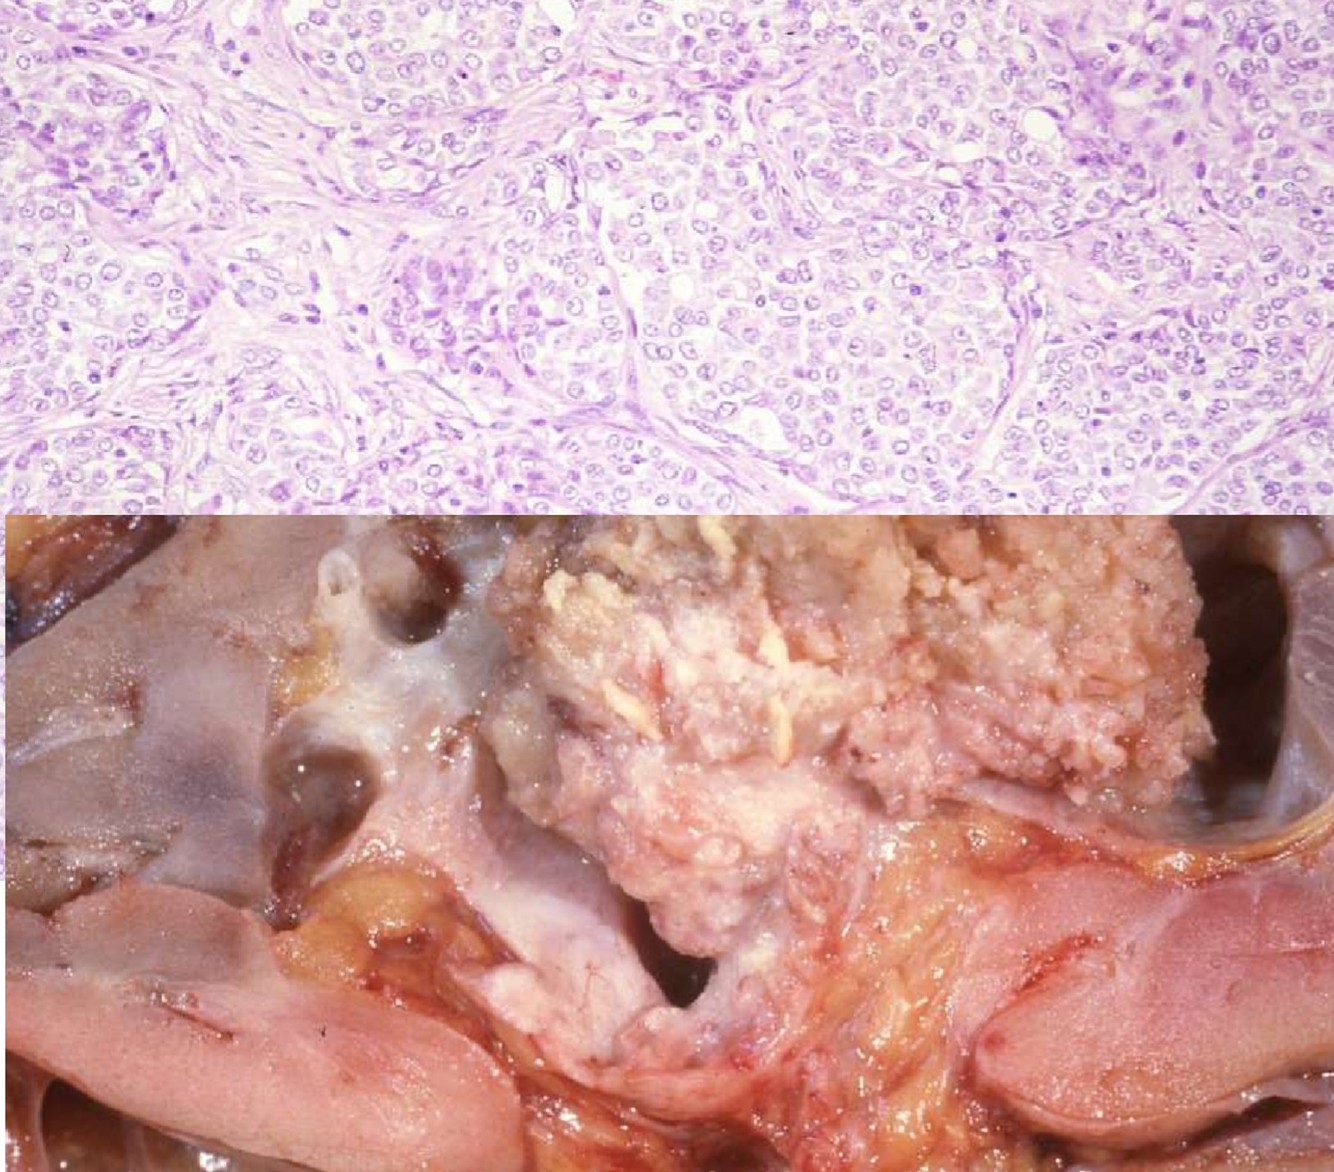

CHROMOPHOBE RCC

- Gross:

- Presents as a cortical neoplasm, classically mahogany brown in color

- MIcro:

- Solid, sheet-like growth pattern

- Clear to eosinophilic cytoplasm with perinuclear halos

- Plant-like cell membrane

- Raisinoid nuclear contours

- Positive Stains

- CK7

- CD117

- Hale colloidal iron

- AE1/AE3

- Negative Stains

- Vimentin

- Carbonic anhydrase IX

- Birt Hogg Dube syndrom: chromophobe/oncocytoma